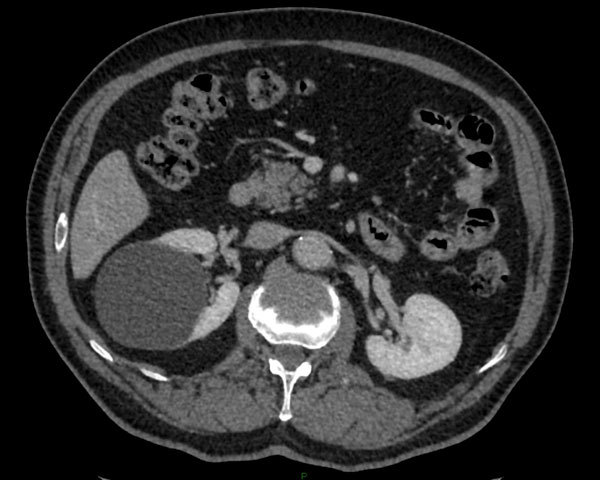

Diagnostic? Quelle maladie héréditaire peut favoriser ce genre de lésion surtout si bilatérales?

Angiomyolipome du rein gauche reconnaissable à sa composante graisseuse.

La Sclérose Tubéreuse de Bourneville donne des agniomyolipomes bilatéraux